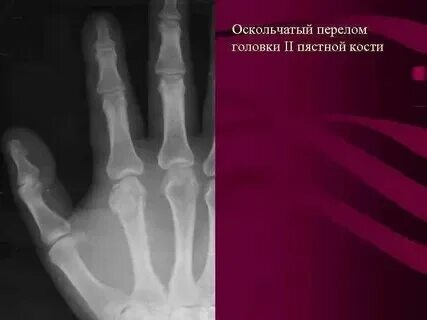

Мкб 10 закрытый перелом пястных костей